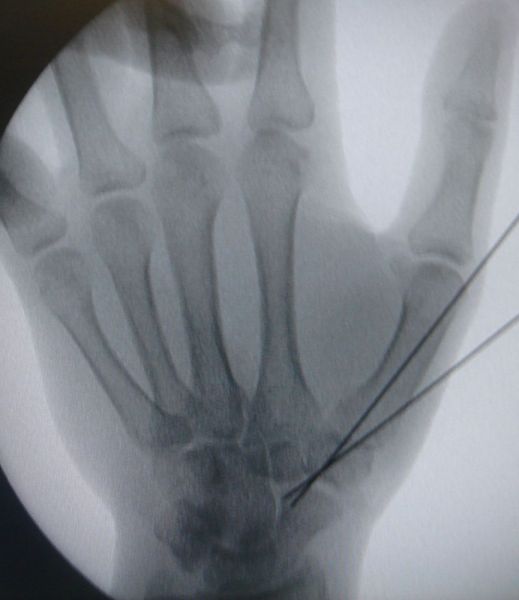

4. Displaced fracture of distal end of the right radius (wrist fracture) in a 63-year-old female.

Treatment. Open reduction internal fixation

I. Before operation, anteroposterior x-ray of the wrist II. Before operation, lateral x-ray of the wrist IIA. Day of procedure, lateral view IIB. Day of procedure, anteroposterior view